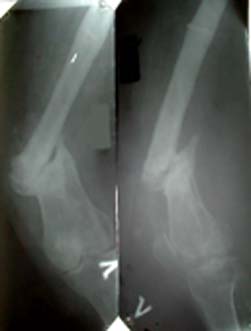

Глубокоуважаемые коллеги. Просьба оказать консультационную помощь Женщина 40 лет. ДТП в 1996: открытый перелом левого бедра, мыщелковый правой голени.

В настоящее время укорочение левой н/конечности 4 см, объем движений левого колена до 70 градусов, патологическая подвижность в области перелома. Планируем дистракцию с помощью аппарата до выравнивания с длиной правой конечности, а вторым этапом резекцию концов отломков бедра и остеосинтез штифтом через интеркондиллярную вырезку.Остеотомию правой б/б кости. Резецированные участки возможно пойдут на заполнение остеотомированной зоны б/берцовой кости. Вопросы по правильности такого планирования, по компоновке аппарата (темп дистракции, жесткость фиксации дистального отломка). Максимов Б.Ю. Сердобск, Пензенская обл.